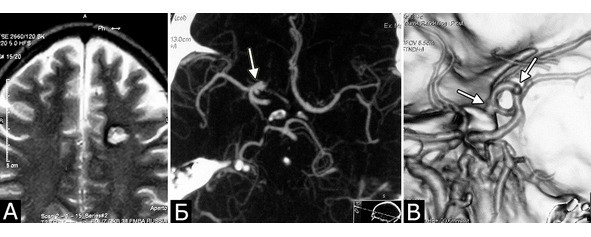

Сочетание каверномы с АВМ выявлено у двух больных, причем в обоих случаях клинические проявления заболевания были обусловлены АВМ, а кавернома явилась случайной находкой (рис. 1).

У 5-х больных с клинически проявившимися каверномами в ходе обследования выявлены бессимптомные артериальные аневризмы передних отделов вилизиева круга (рис. 3). Обращал на себя внимание тот факт, что в 4-х случаях аневризмы были множественными.

Рис. 1.Б-ная Г., 27 лет. Сочетанная сосудистая патология мозга: КМ передне-медиальных отделов височной доли справа (А – МРТ, режим Т1; Б – МРТ, режим Т2); АВМ медиальных отделов лобно-теменной области справа (В – МРТ, режим Т2;Г – МРТ-АГ). Клиническое течение: редкие вторично-генерализованные судорожные эпилептические припадки, начинающиеся с судорог в левых конечностях

Рис. 3.Б-ной К-ов, 37 лет. Сочетанная сосудистая патология мозга: КМ глубинных отделов лобной доли слева (А – МРТ, режим Т2); две аневризмы ВСА справа (Б, В – СКТ-АГ, аневризмы указаны стрелками). Течение болезни:за 6 месяцев до поступления перенес два генерализованных судорожных припадка. При МРТ выявлена КМ лобной доли слева, которая послужила причиной припадков. При СКТ-АГ выявлены две аневризмы ВСА справа (случайная находка). Лечение:1-ая операция – клипирование двух аневризм ВСА справа. 2-ая операция – удаление каверномы левой лобной доли